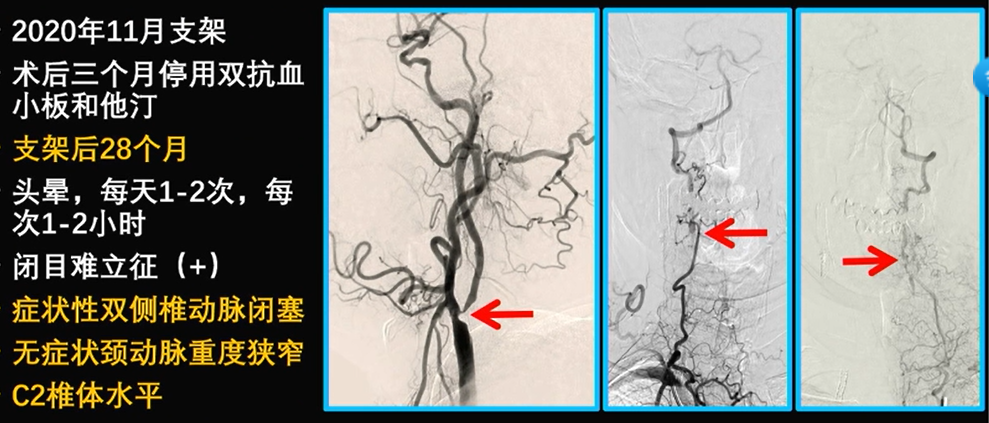

病例5:右侧颈动脉重度狭窄,双侧椎动脉闭塞

治疗方案:冠脉支架和颈部血运重建(心脑同治),间隔2-4天。颈部血运重建术,采用补片CEA治疗ISR,CCA-RA-V2搭桥(新术式),治疗双侧椎动脉闭塞,有效提升后循环血供。